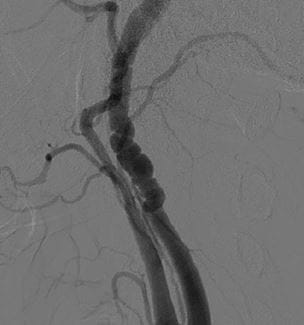

Internationally Recognized Expert on Fibromuscular Dysplasia Joins UH

FMD primarily affects women, now recognized as more common than previously thought - Innovations in Cardiovascular Medicine & Surgery - Winter 2019